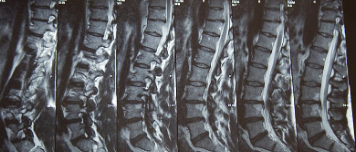

허리디스크를 정확하게 진단하기 위해서는 엑스레이로는 힘들며, MRI를 통해 검사해야 정확하게 볼 수 있습니다.

MRI가 몸에 좋지 않지만 허리 통증으로 엑스레이만 진행 할 경우 오진이 많아 지속적인 통증이 계속 된다면 허리디스크를 의심하고 MRI 검사를 한번 받아보시길 권유드립니다.